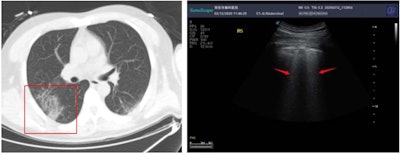

By the fourth day following his diagnosis, Chen's ultrasound scan on his left side showed an increasingly thickened pleural line and two subpleural consolidations. Video courtesy of Dr. Yale Tung Chen.

In a March 12 letter in Intensive Care Medicine, researchers from Changsha, China, were among the first to describe how they used lung ultrasound to monitor more than a dozen patients with COVID-19 infections. The letter documented five characteristic findings of COVID-19 pneumonia on ultrasound scans that would later be known as hallmark signs of the new disease, including a thickened pleural line and a variety of B-line patterns.